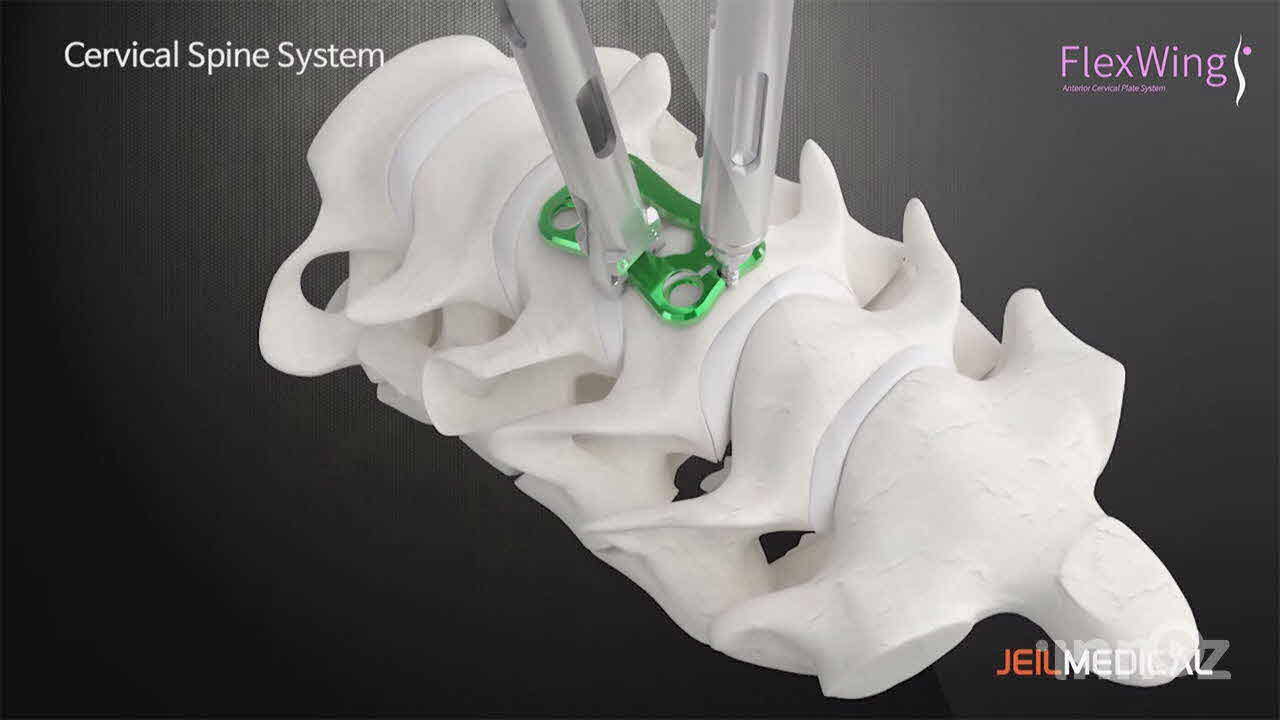

제일메디칼

제일메디칼

제일메디칼

제일메디칼

제일메디칼